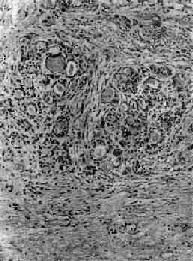

图15-8 纤维性甲状腺炎 甲状腺滤泡萎缩,纤维组织明显增生,有少量淋巴细胞浸润

四、甲状腺炎甲状腺炎可分为急性、亚急性、慢性三种。急性甲状腺炎为细菌感染引起的急性间质炎或化脓性炎,由于甲状腺对细菌感染抵抗力强,故很少见。亚急性及慢性甲状腺炎是独立的具有特征性病变的疾病。 (一)亚急性甲状腺炎 亚急性甲状腺炎(subacute thyroiditis)又称肉芽肿性或巨细胞性甲状腺炎,一般认为病因是病毒感染,具有发热等病毒感染症状,曾分离出腮腺炎、麻疹、流感病毒,甲状腺出现疼痛性结节,病程为6周到半年,然后自愈。本病女性多于男性,多在30岁左右发病。 肉眼观,甲状腺呈不均匀轻度肿大,质硬,常与周围粘连,切面可见灰白色坏死或纤维化病灶。镜下可见分布不规则的滤泡坏死破裂病灶,其周围有急性、亚急性炎症,以后形成类似结核结节的肉芽肿。肉芽肿中心为不规则的胶质碎块伴有异物巨细胞反应,周围有巨噬细胞及淋巴细胞。以后肉芽肿纤维化,残留少量淋巴细胞浸润。本病初期,由于滤泡破坏甲状腺素释放增多,可出现甲状腺毒症;晚期如果甲状腺有严重的破坏乃至纤维化,可出现甲状腺功能低下。 (二)慢性甲状腺炎 1.慢性淋巴细胞性甲状腺炎(chronic lymphocytic thyroiditis)亦称桥本甲状腺炎,为自身免疫病。患者甲状腺肿大,功能减退。甲状腺结构为大量淋巴细胞、巨噬细胞所取代,滤泡萎缩,结缔组织增生。本病基本缺陷是抗原特异性T抑制细胞减少,致细胞毒性T细胞得以攻击破坏滤泡细胞,且TH细胞参与B细胞形成自身抗体,引起自身免疫反应。 2.纤维性甲状腺炎(fibrous thyroiditis)又称Riedel甲状腺肿,甚少见,主要发生在中年妇女,病因不明。病变多从一侧开始,甲状腺甚硬,表面略呈结节状,与周围明显粘连,切面灰白。镜下,甲状腺滤泡明显萎缩,纤维组织明显增生和玻璃样变,有少量淋巴细胞浸润(图15-8)。临床常有甲状腺功能低下。